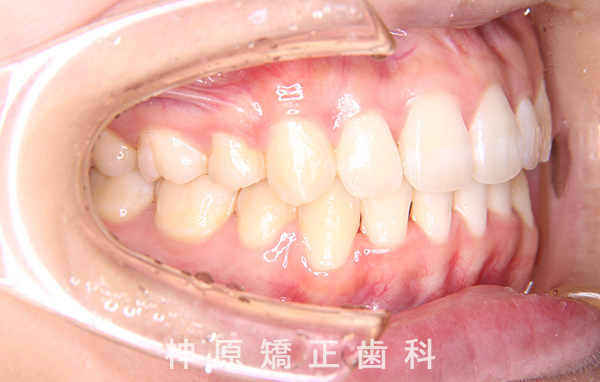

上顎前突症例(出っ歯)

Maxillary Protrusion Case

18歳 女性

症例01

- 主訴

- 上の歯が出ている

- 初診時年齢

- 18歳4ヶ月

初診時